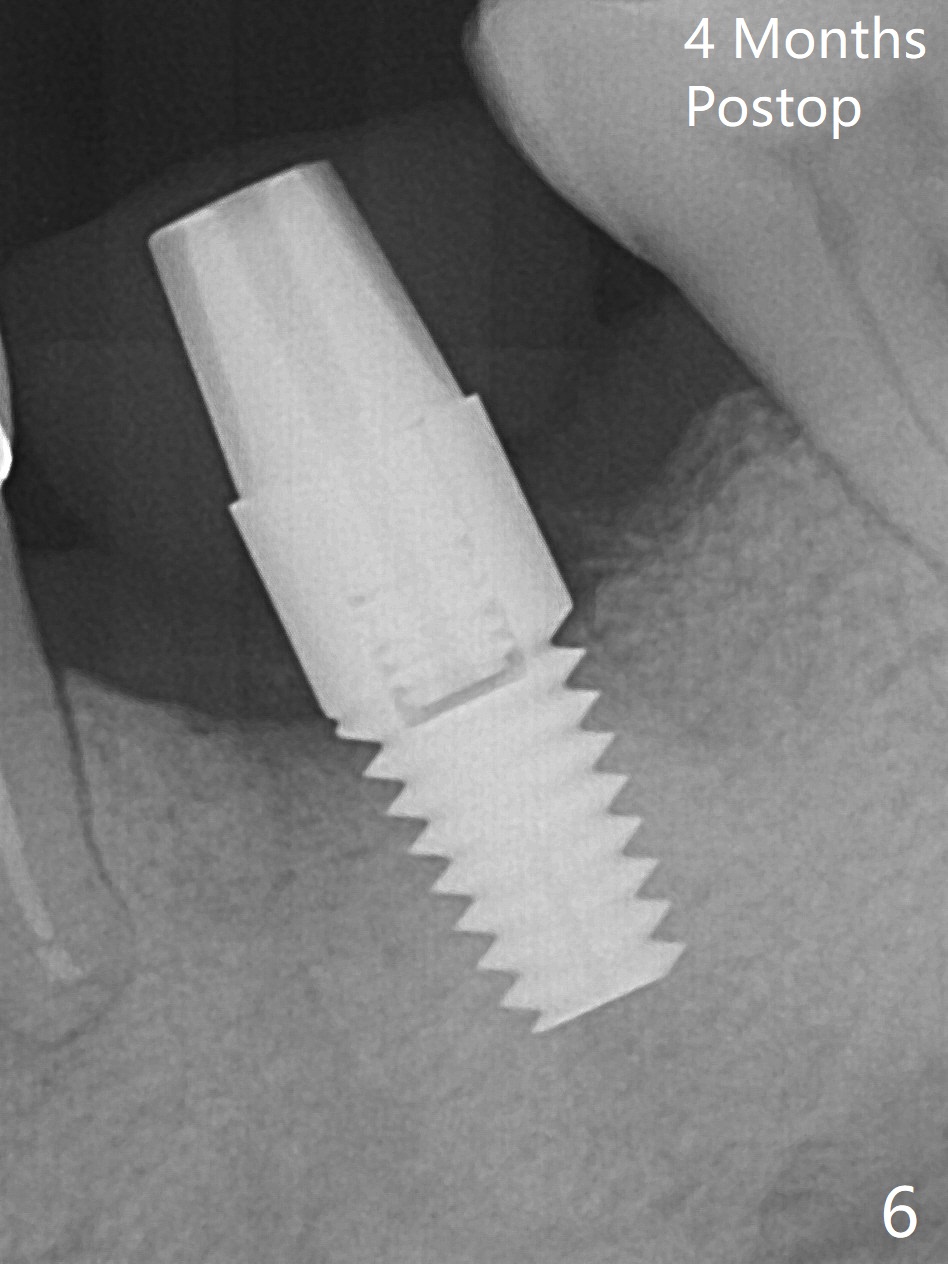

After extraction of the tooth #19 with mesial root fracture (Fig.1 ^) and curettage, the initial osteotomy in the septum is found to need to be distalized (Fig.2 arrow). Following sequential osteotomy, a 5x17 mm tap cannot reach the expected depth (Fig.3 yellow dashed line) because of the dense bone. A shorter implant is placed with >60 Ncm (Fig.4). An immediate provisional is fabricated after placement of a 4.5x5 mm abutment and Vanilla/Osteogen graft (Fig.5 *). The mesial and distal sockets heal 4 months postop (Fig.6). The bone density in the mesial and distal sockets continues to increase when a crown is cemented (~4.5 months postop, Fig.7). The implant at #19 was placed in the middle of the bone (Fig.8).